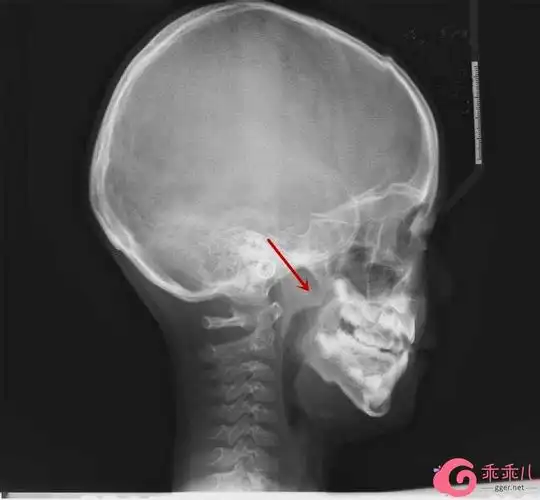

孙晓卫说,鼻骨侧位x线片相对来说比较经济,便捷,是诊断鼻骨骨折重要

鼻骨骨折影像学诊断与鉴别

鼻骨骨折影像学诊断

鼻骨常见骨折征象